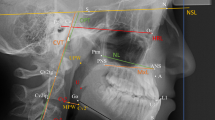

In addition to conventional cephalometric variables, some linear measurements were performed by projecting landmarks on the vertical lines perpendicular to the Frankfurt Horizontal (FH) plane through the sella (S), the pterygomaxillary fissure (Ptm), or nasion (N). The cephalometric measurements used in the present study were the same as described in the previous study [18].

Cephalometric analysis derived from the original analysis of Björk and Skieller [16] was performed to evaluate facial mask effects by decomposing T1-T2 changes into maxillary skeletal growth and maxillary molar movement. The structural superimposition method for this analysis was applied as described previously [16, 18] and is briefly explained below.

Figure 1 shows superimposition of the T1 and T2 tracings on the maxillary internal stable structure, the anterior contours of the zygomatic processes. Tracing and superimpositions were performed manually. “T1 tracing” was superimposed on the cranial base of the T2 tracing. “Superimposed T1 tracing” was superimposed on the maxillary internal stable structure of the T2 tracing. The dental component was represented as the distance between measurement points of the molar on the T2 tracing and the superimposed T1 molar on the T2 tracing. The skeletal component was represented as the distance between measurement points of the molar on the T1 tracing and the superimposed T1 molar on the T2 tracing. The amount and direction of rotation of the maxilla (maxillary rotation) were measured as the angle between the sella-nasion (SN) lines of the superimposed T1 tracing and the T2 tracing on superimposition. A positive value for maxillary rotation means counter-clockwise (backward) rotation of the maxilla.

Left: Superimposition of pre-treatment (initial, T1) and posttreatment (final, T2) tracings on the cranial base. Right: Superimposition of T1 and T2 tracings on the maxillary internal stable structure, the anterior contour of the zygomatic processes (shown by a black broken line). The maxillary dental component and maxillary skeletal component are represented. The maxillary rotation was measured as the angle between the sella-nasion (SN) lines of T1 and T2 tracings on the superimposition. Ptm: the pterygomaxillary fissure; A: point A